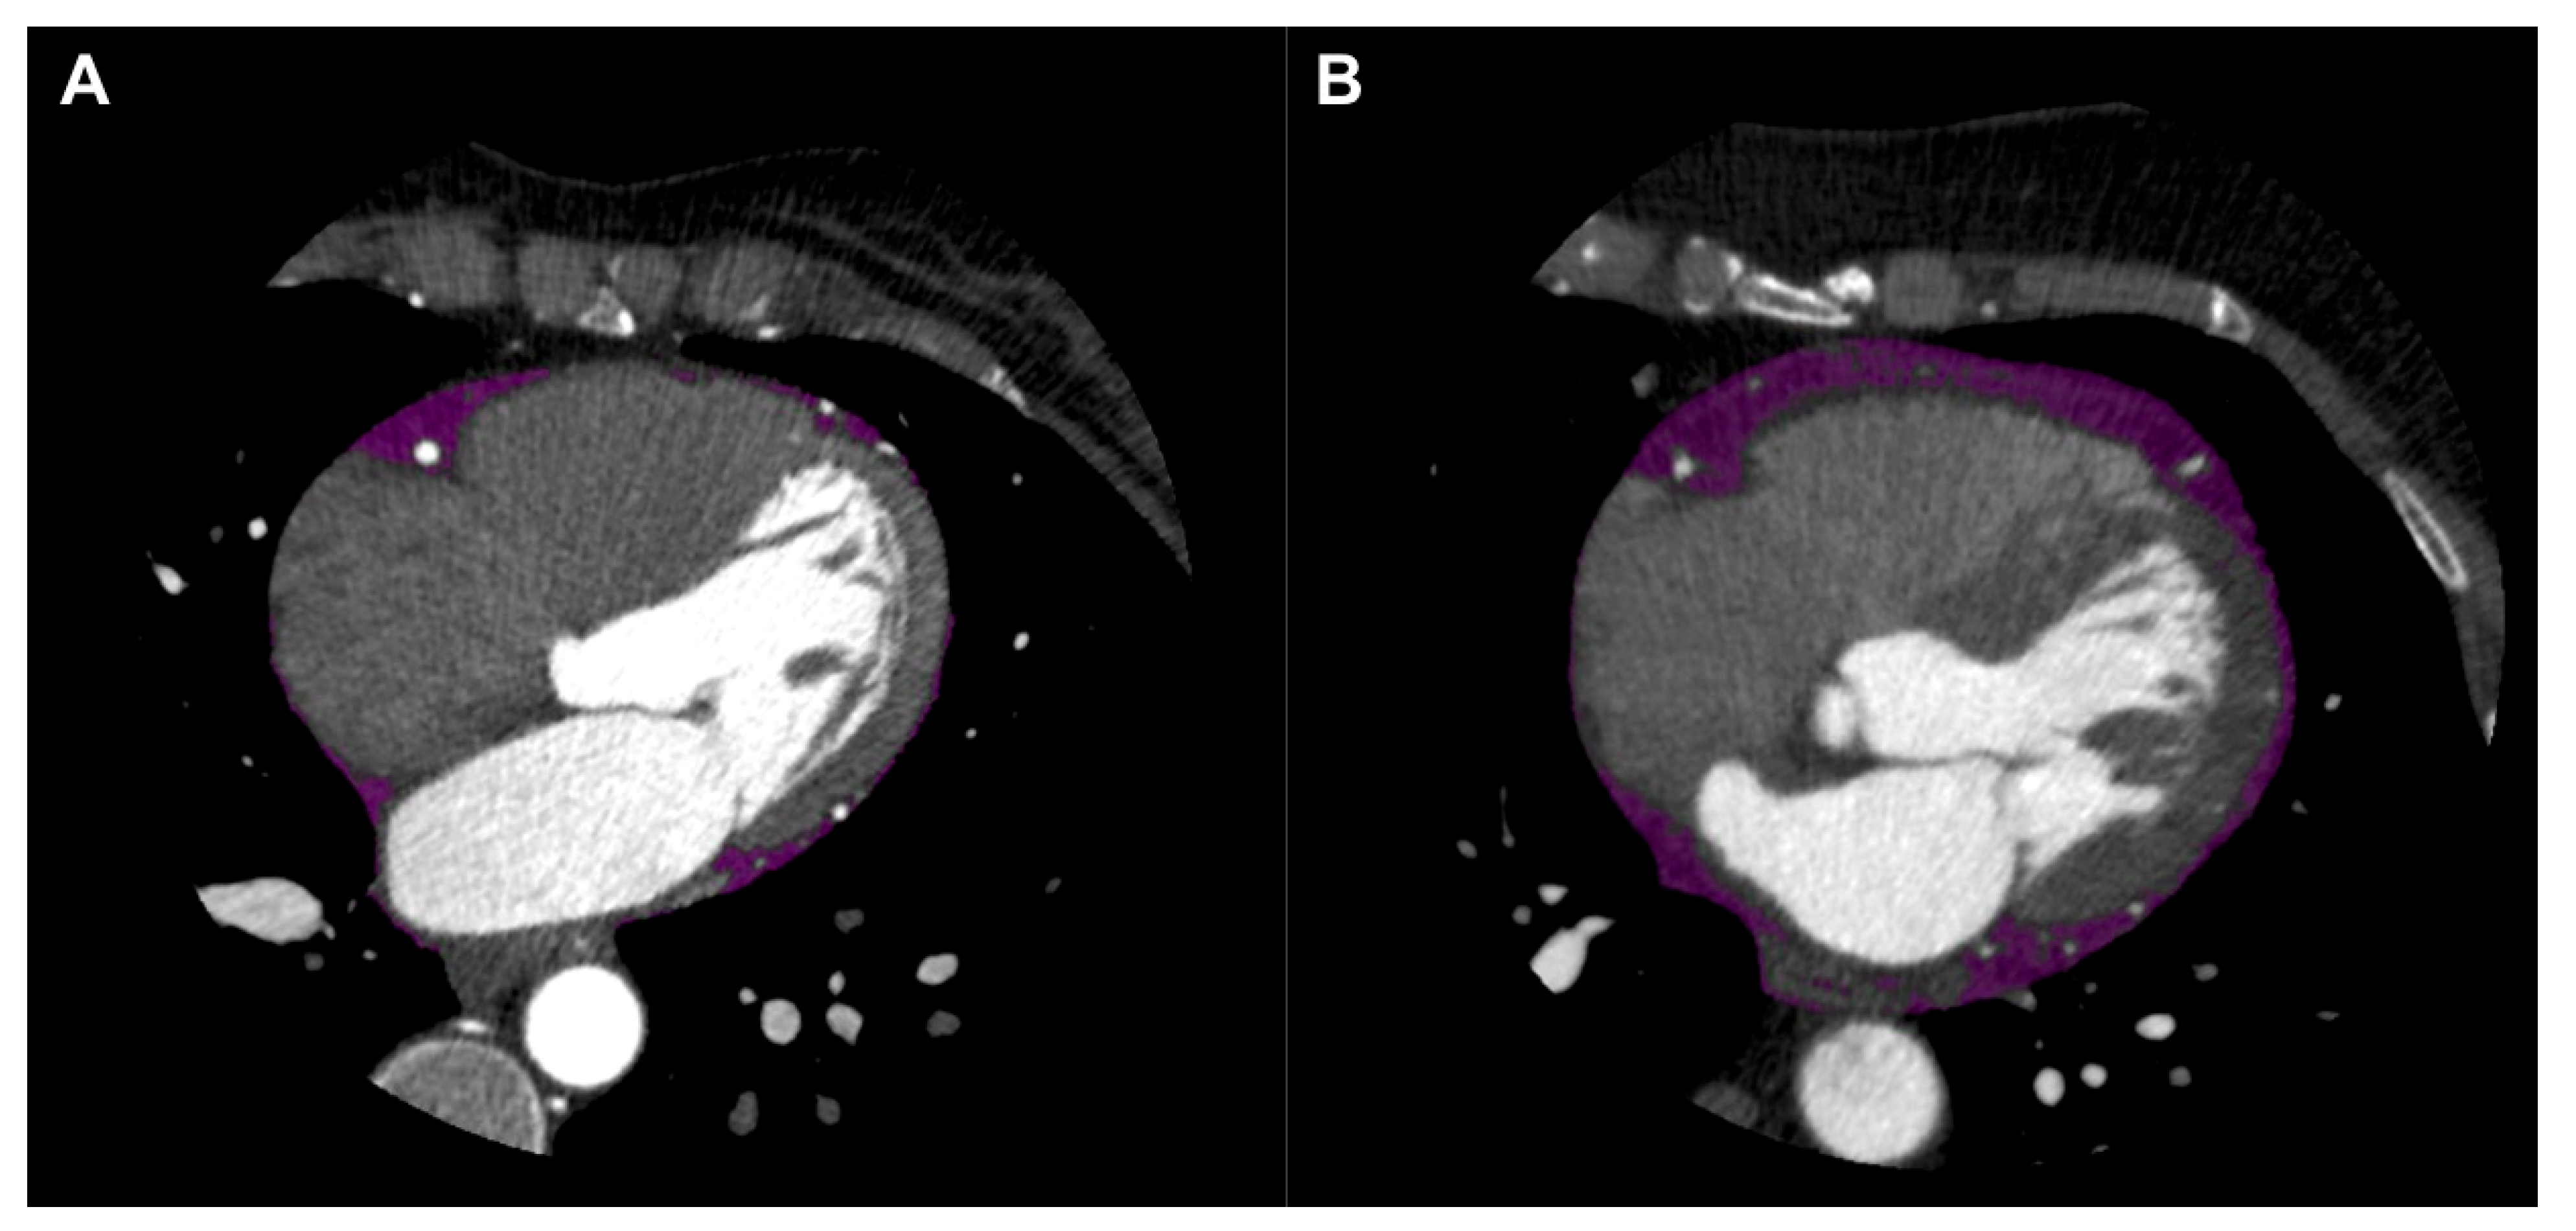

5.1. EAT Quantification